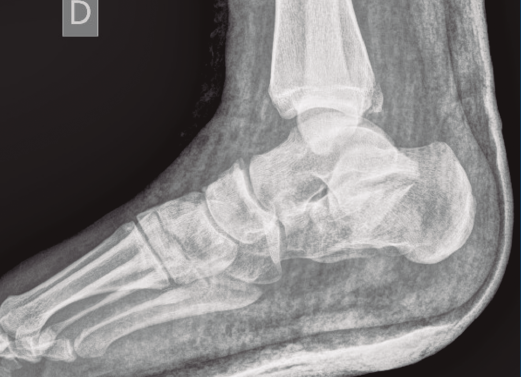

Figura 1. Luxación del astrágalo en mortaja tibioperonea, fractura maléolo peroneo y espacio subperoneo ocupado por calcáneo.

Se trata de un varón de 19 años que ingresa en reanimación tras precipitarse desde una altura de aproximadamente 10 metros. El paciente presenta una fractura estallido de L3 con afectación del canal medular junto con una fractura del vértice inferior de L4, así como una fractura luxación de calcáneo, asociada a una fractura del maléolo peroneo y del maléolo tibial posterior (Figuras 1 a 6) diagnosticadas mediante TC total body (por eso no se dispone de radiografías simples al momento del ingreso). Como podemos comprobar, se trata de una fractura de doble trazo de tipo hundimiento/depresión de la carilla articular (Figuras 5 y 6).

Figura 7. Radiografía lateral de pie y tobillo; se evidencia fractura de calcáneo y de maléolo tibial posterior.